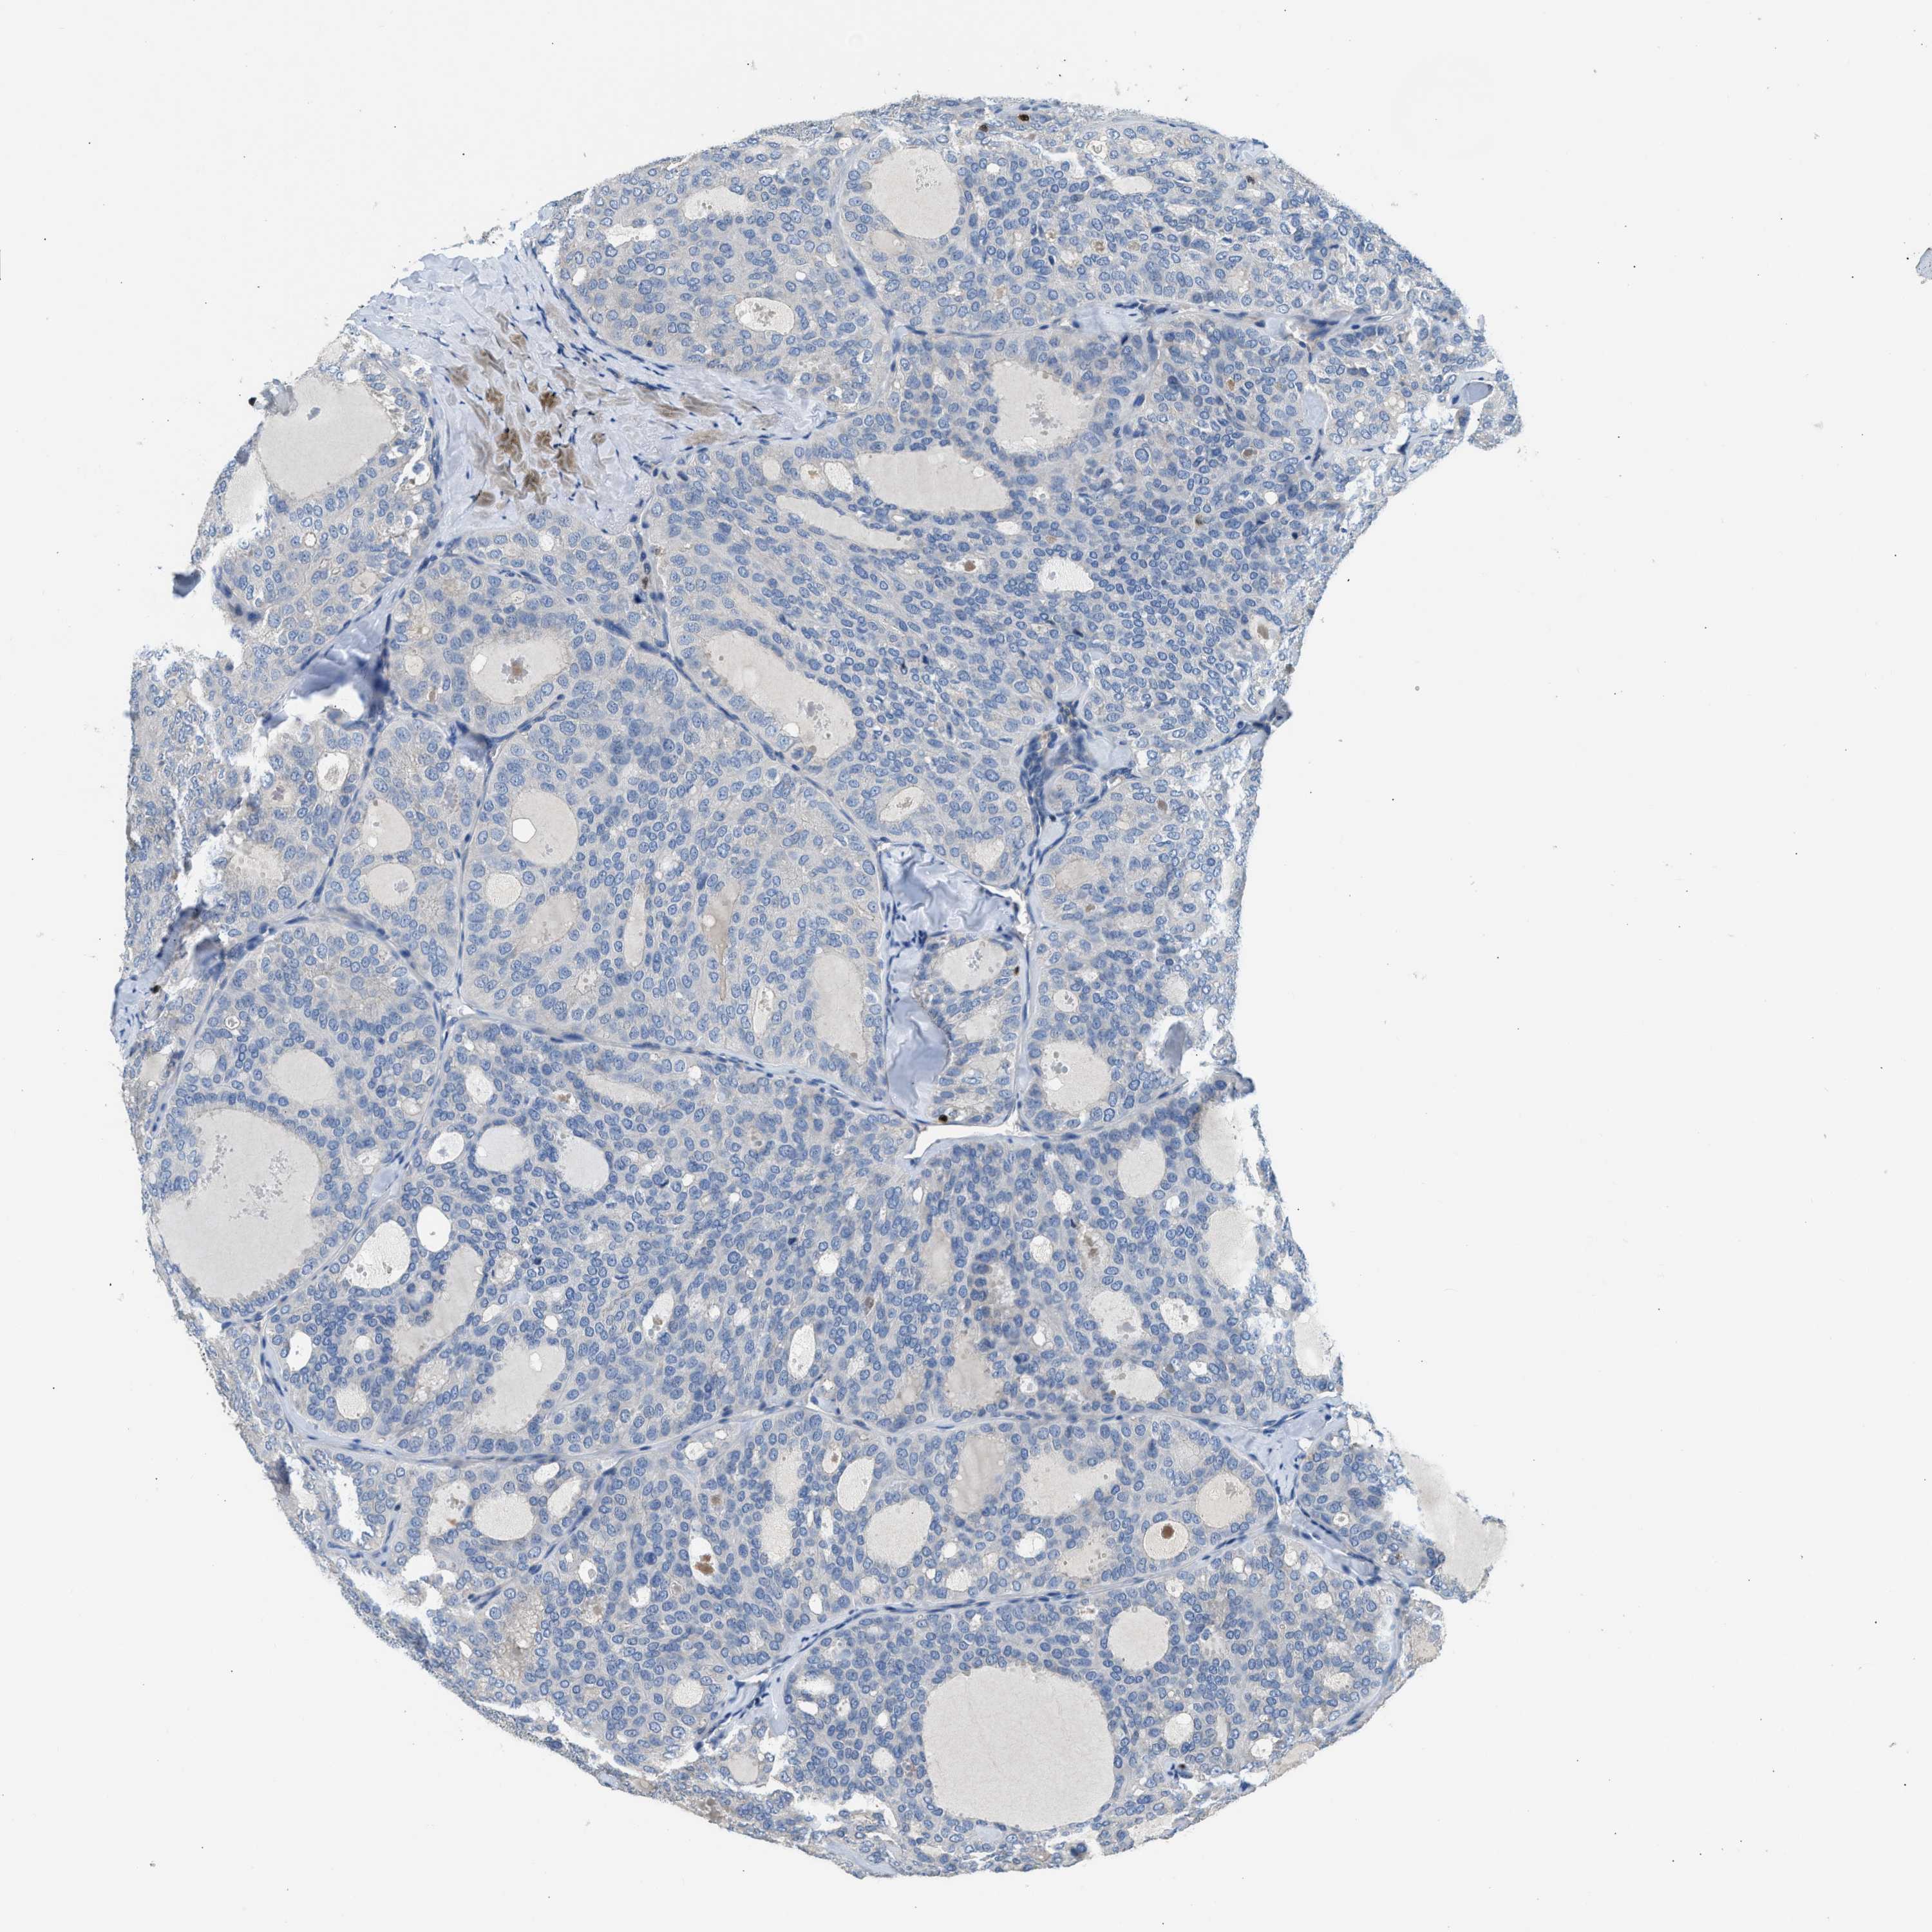

THYROID CANCER - Protein expressioni

A mouse-over function shows sample information and annotation data. Click on an image to view it in a full screen mode. Samples can be filtered based on level of antibody staining by selecting one or several of the following categories: high, medium, low and not detected. The assay and annotation is described here.

Note that samples used for immunohistochemistry by the Human Protein Atlas do not correspond to samples in the TCGA dataset.

Antibody stainingi

Antibody staining in the annotated cell types in the current human tissue is reported as not detected, low, medium, or high, based on conventional immunohistochemistry profiling in selected tissues. This score is based on the combination of the staining intensity and fraction of stained cells.

Each image is clickable and will lead to virtual microscopy that enables deeper exploration of all samples and also displays staining intensity scores, fraction scores and subcellular localization as well as patient and tissue information for each sample.

Antibody HPA018322

Staining

High

Medium

Low

Not detected

Intensity

Strong

Moderate

Weak

Negative

Quantity

>75%

75%-25%

<25%

None

Location

Nuclear

Cytoplasmic/membranous

Cytoplasmic/membranous,nuclear

Papillary adenocarcinoma, NOS

Follicular adenoma carcinoma, NOS